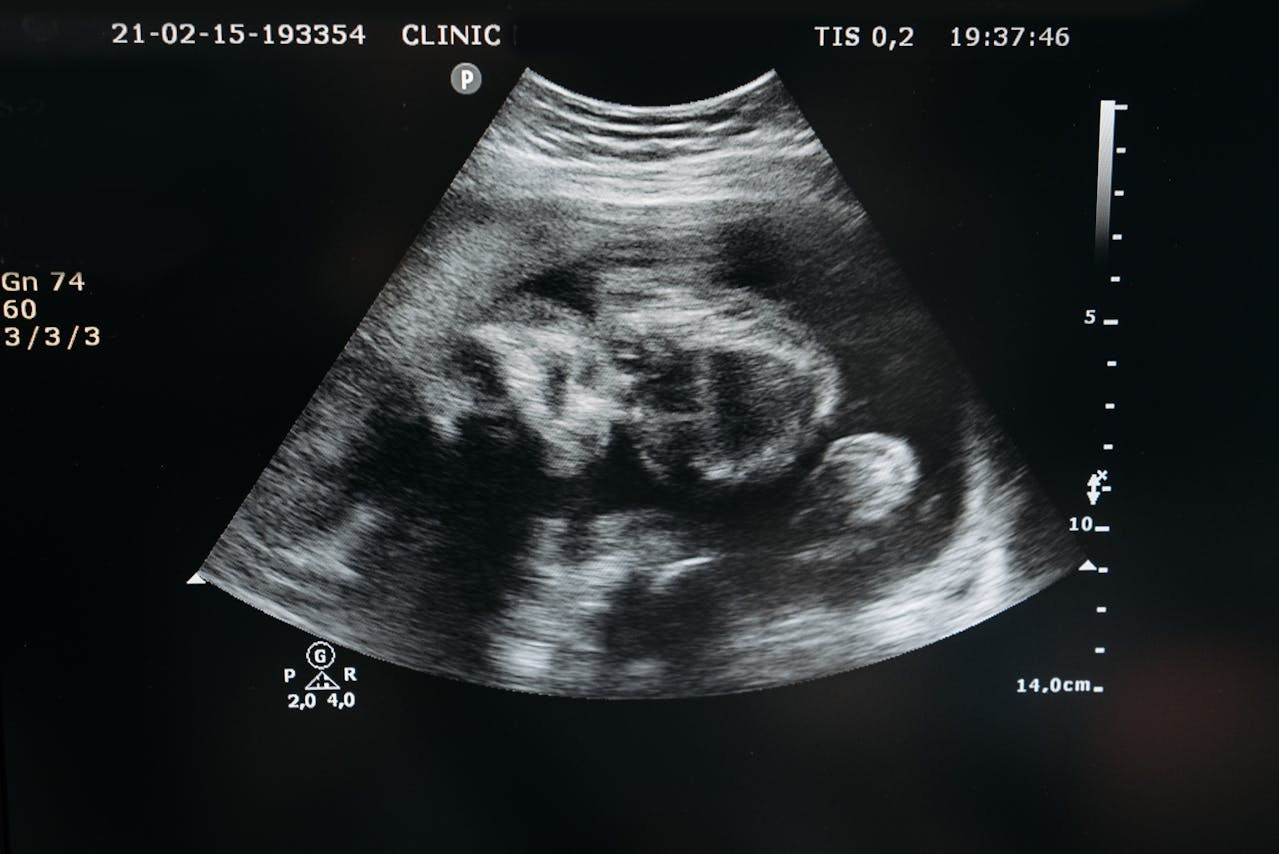

Ecografias Actualmente entre la semana 11-13s y formando parte del test combinado (cribado de cromosomopatías, por ejemplo síndrome de Down) se debe realizar a todas las gestantes

Ecografía Morfológica. Ecografía de las 20 semanas. Es la evaluación pormenorizada de la morfología fetal con el objetivo de descartar la presencia de malformaciones estructurales